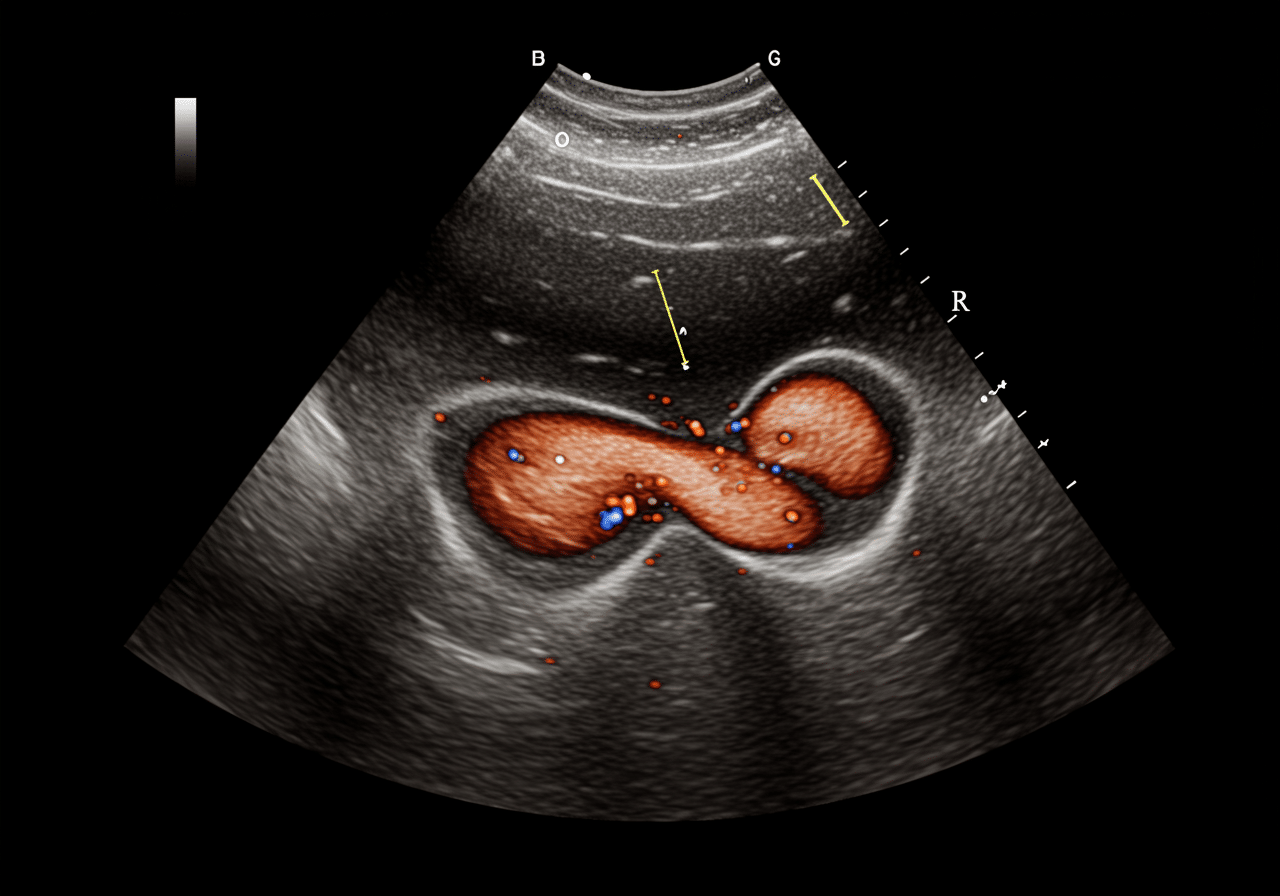

Priority ER's diagnostic capabilities for pelvic ultrasound for ectopic pregnancy or ovarian torsion exceed Joint Commission standards for emergency departments[14], featuring high-resolution transvaginal ultrasound probes (5-9 MHz) enabling visualization of gestational sac at β-hCG 1500-2000 mIU/mL (discriminatory zone), identification of yolk sac and fetal pole confirming intrauterine pregnancy excluding ectopic diagnosis, and color Doppler assessment detecting ovarian blood flow (present: rules out torsion; absent: confirms torsion) with 92% sensitivity when clinical suspicion high. Our emergency physicians trained in emergency ultrasound perform systematic evaluation including visualization of adnexa identifying ectopic mass with "ring of fire" vascular sign (90% specific for ectopic), assessment for free fluid in Morrison's pouch and pelvis indicating hemoperitoneum from rupture, and ovarian Doppler demonstrating whirlpool sign (twisted vascular pedicle) pathognomonic for torsion[15]. The integration of quantitative β-hCG correlation with ultrasound findings determines next steps: IUP visualized (excludes ectopic), β-hCG >discriminatory zone without IUP (presumed ectopic), or β-hCG below discriminatory zone (follow-up in 48 hours assessing doubling).

Advanced assessment through our comprehensive diagnostic capabilities provides progesterone level measurement (>25 ng/mL suggests viable IUP, <5 ng/mL suggests nonviable), serial β-hCG monitoring determining appropriate rise (normal: doubles every 48-72 hours in early pregnancy), and diagnostic dilation and curettage when β-hCG plateau suggests nonviable pregnancy but location uncertain. For ovarian torsion evaluation, our emergency physicians assess ovarian size (normal: 3-4 cm; >5 cm increases torsion risk), identify dermoid cyst or other masses predisposing to torsion, and evaluate uterine Doppler distinguishing torsion from pelvic inflammatory disease or appendicitis presenting similarly. This comprehensive approach explains why the American College of Obstetricians and Gynecologists mandates transvaginal ultrasound as gold standard for suspected ectopic pregnancy, providing definitive visualization of gestational location determining whether methotrexate medical management versus surgical intervention required preserving fertility while preventing life-threatening rupture.